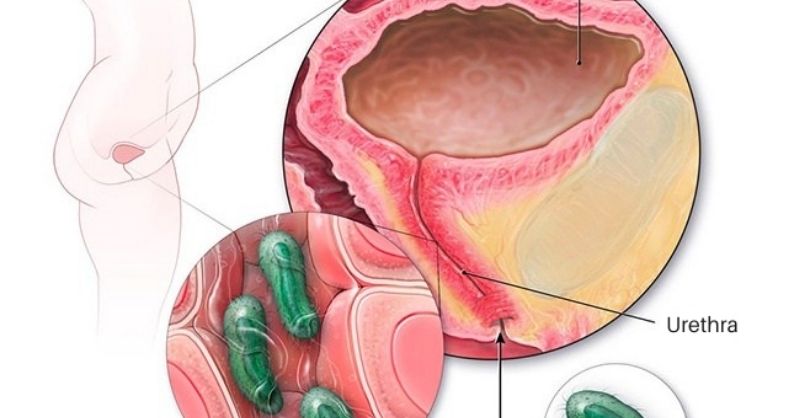

7 Effective Remedies to Treat a Urinary Tract Infection

Urinary tract infections, especially cystitis, are common and often painful. They tend to come back frequently and need quick treatment to prevent complications. Although antibiotics are commonly...